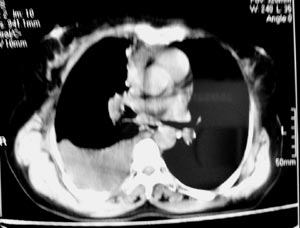

右侧胸膜结节状增厚伴胸腔积液及纵隔、腋窝淋巴结肿大,考虑胸膜间皮瘤可能性大;建议胸膜活检。

右侧中央型肺癌合并阻塞性肺炎及右侧胸膜转移。

右侧肺门淋巴结肿大,伴大量胸腔积液,同侧胸膜结节样增厚,有胸膜粘连,考虑肺癌.